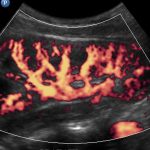

O Doppler é um recurso especial dos exames de ultrassonografia que permite a detecção e avaliação de estruturas em movimento, em especial no corpo humano, do fluxo sanguíneo.

- Detecção e caracterização de vasos no interior de lesões ( por exemplo, no interior de

nódulos tireoide, nódulos mamários, cistos de ovário, miomas uterinos, pólipos endometriais, nódulos hepáticos, dentre outros … ). - Avaliação da quantidade e padrão de vascularização presente no interior de órgãos ( por exemplo, no interior da tireóide, de linfonodos, de glândulas salivares, dentre outros … )

- Avaliação da integridade do sistema arterial ( presença de placas ou processos obstrutivos em carótidas e vertebrais, artérias renais, aorta abdominal e artérias ilíacas, artérias em membros superiores e inferiores, … )

- Avaliação da integridade do sistema venoso ( sinais de trombose em membros, varizes, … )

- Avaliação da integridade de rim transplantado ou de fístula arteriovenosa para hemodiálise

- Avaliação de bem-estar fetal ou fatores de risco para Doença Hipertensiva Específica da Gravidez ( DHEG ou pré-eclâmpsia )